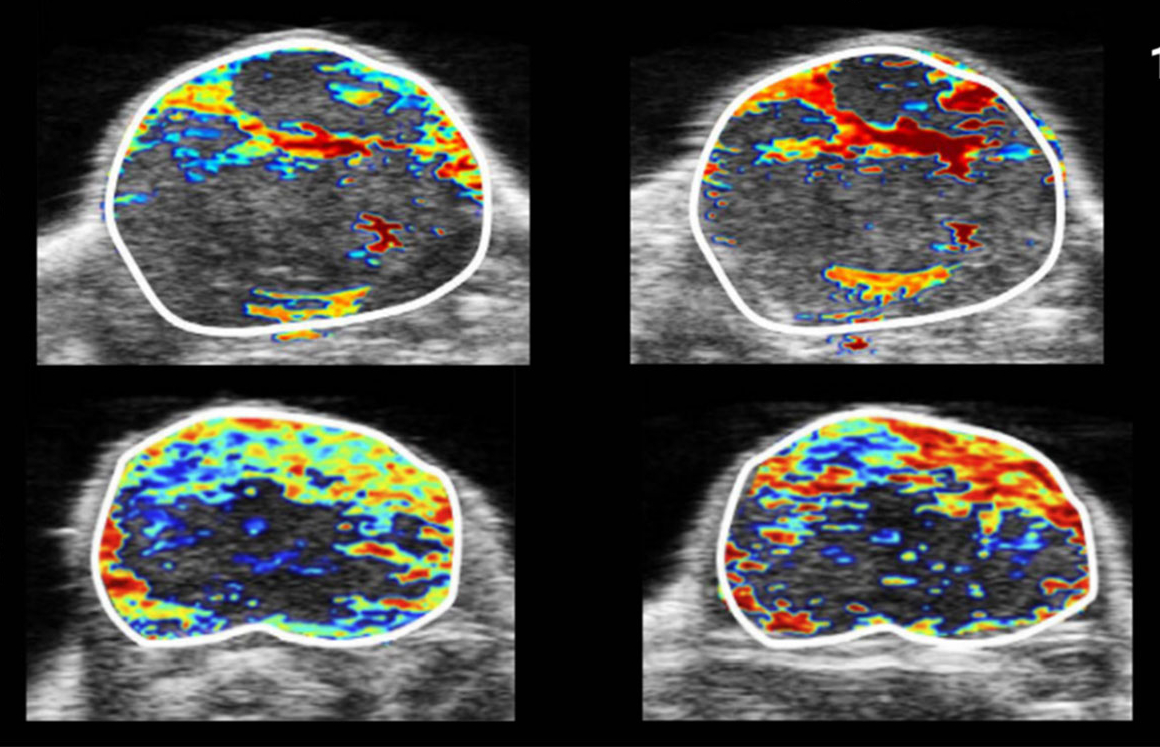

Unleashing the Clinical Potential of Photoacoustic Imaging

Photoacoustic imaging (PAI) is a promising hybrid imaging modality that combines the strengths of optical and ultrasound imaging. PAI leverages the rich contrast of optical imaging with the deep tissue penetration and spatial resolution of ultrasound. This dual capability enables it to capture both structural and functional information from biological tissues in real time.